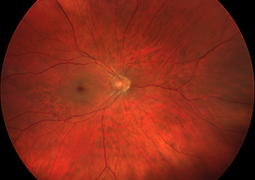

- Radiation Maculopathy in Patients with Malignant Melanoma of the Corpus Ciliare and Choroidea Following One-Day Session of Stereotactic Radiosurgery